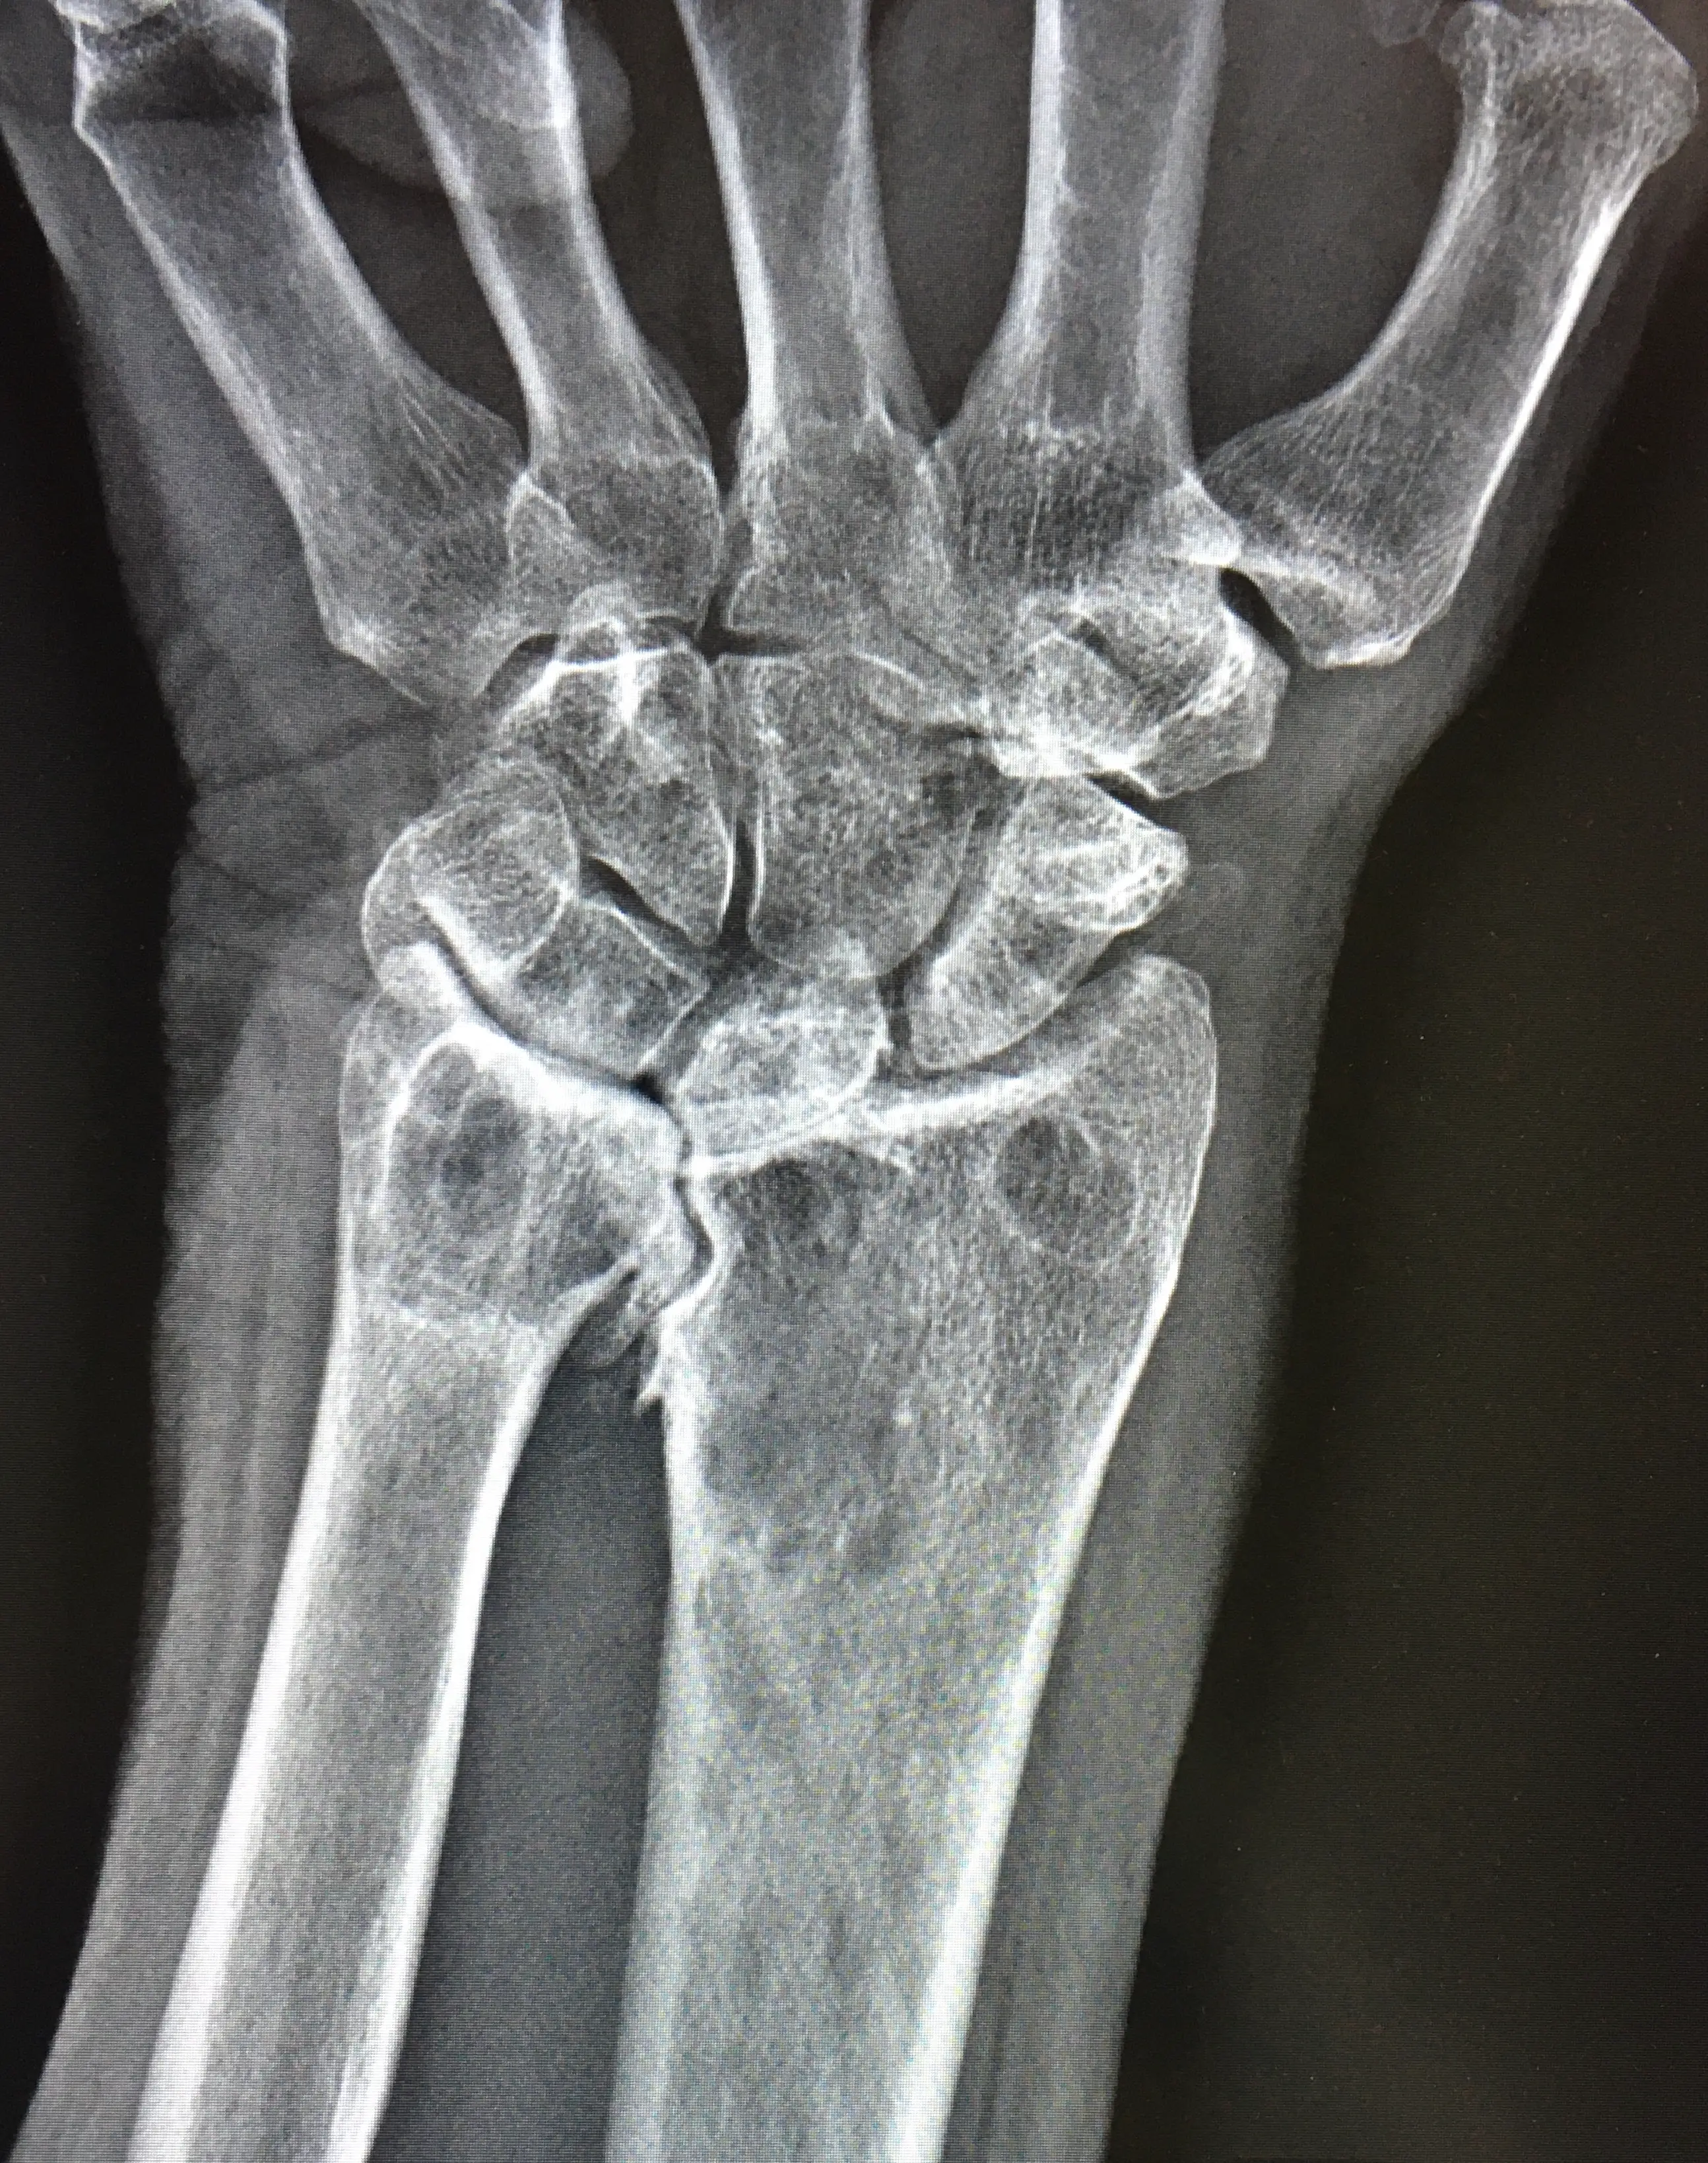

МРТ лучезапястного сустава

Визуализация костей лучезапястного сустава, суставного диска, сухожилий, связок, регионарных мышц.

— Травматические повреждения элементов сустава